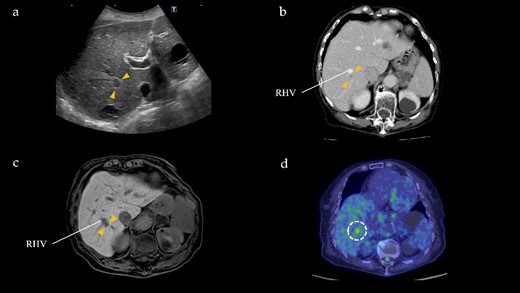

One year after the initial surgery, a tumor in Segment 7 (S7) of the liver was detected on CT. The serum hepatitis B surface antigen and hepatitis C antibody test results were negative. Laboratory data on admission, including liver function test results, were unremarkable, including carcinoembryonic antigen (CEA) and CA19-9 levels. The imaging results are shown in Fig. 2. Abdominal ultrasonography revealed a hypoechoic, 10 mm diameter mass in the right hepatic lobe (S7). Plain CT revealed a low-density area in the right hepatic lobe (S7), presenting as a mass with reduced density in both the early and portal phases with contrast enhancement. Gadoxetic acid (Gd-EOB-DTPA)-enhanced MRI (EOB-MRI) revealed a slightly low-intensity lesion on T1-weighted images and a high-intensity lesion on T2-weighted images. Positron emission tomography–computed tomography (PET/CT) showed fluorodeoxyglucose (FDG) accumulation (maximum standardized uptake value, SUVmax = 3.91) in a nodule of the liver S7. We diagnosed this lesion as CRLM at S7. The patient underwent right posterior sectionectomy. The right posterior Glissonian pedicle was isolated extrahepatically. The tumor was adjacent to the right hepatic vein (RHV); however, no invasion was observed. The operative time was 302 min, and the estimated blood loss was 321 ml. Macroscopic examination revealed a white mass measuring 8 × 9 × 8 mm. Microscopic findings revealed clusters of lymphocytes with multiple germinal centers (shown in Fig. 3). There was no atypia in the lymphocytes, and aggregation was thought to be due to lymphocyte reactivity, consistent with RLH. There was a portal vein area at the edge of the tumor, and bile ducts were identified, but there were no findings suggestive of malignancy such as degeneration or irregular arrangement. According to these findings, this patient was diagnosed as RLH. The patient was discharged 11 days postoperatively with good progress. The patient showed no signs of recurrence at 40 months after the initial surgery.

Radiographical findings of Segment 7 lesion in the liver. (a) On abdominal ultrasound, a hypoechoic tumor, measuring 10 mm (arrows), is identified in Segment 7. (b) Contrast-enhanced computed tomography indicates a 10 mm, hypodensity lesion located in Segment 7 (arrows) at portal phase. This lesion is close to the RHV. (c) Gadoxetic acid-enhanced magnetic resonance imaging shows a 10 mm, hypointensity lesion (arrows) in Segment 7 adjacent to the RHV at hepatic phase. (d) PET/CT reveals FDG accumulation (maximum standardized uptake value, SUVmax = 3.91) in the Segment 7 nodule.